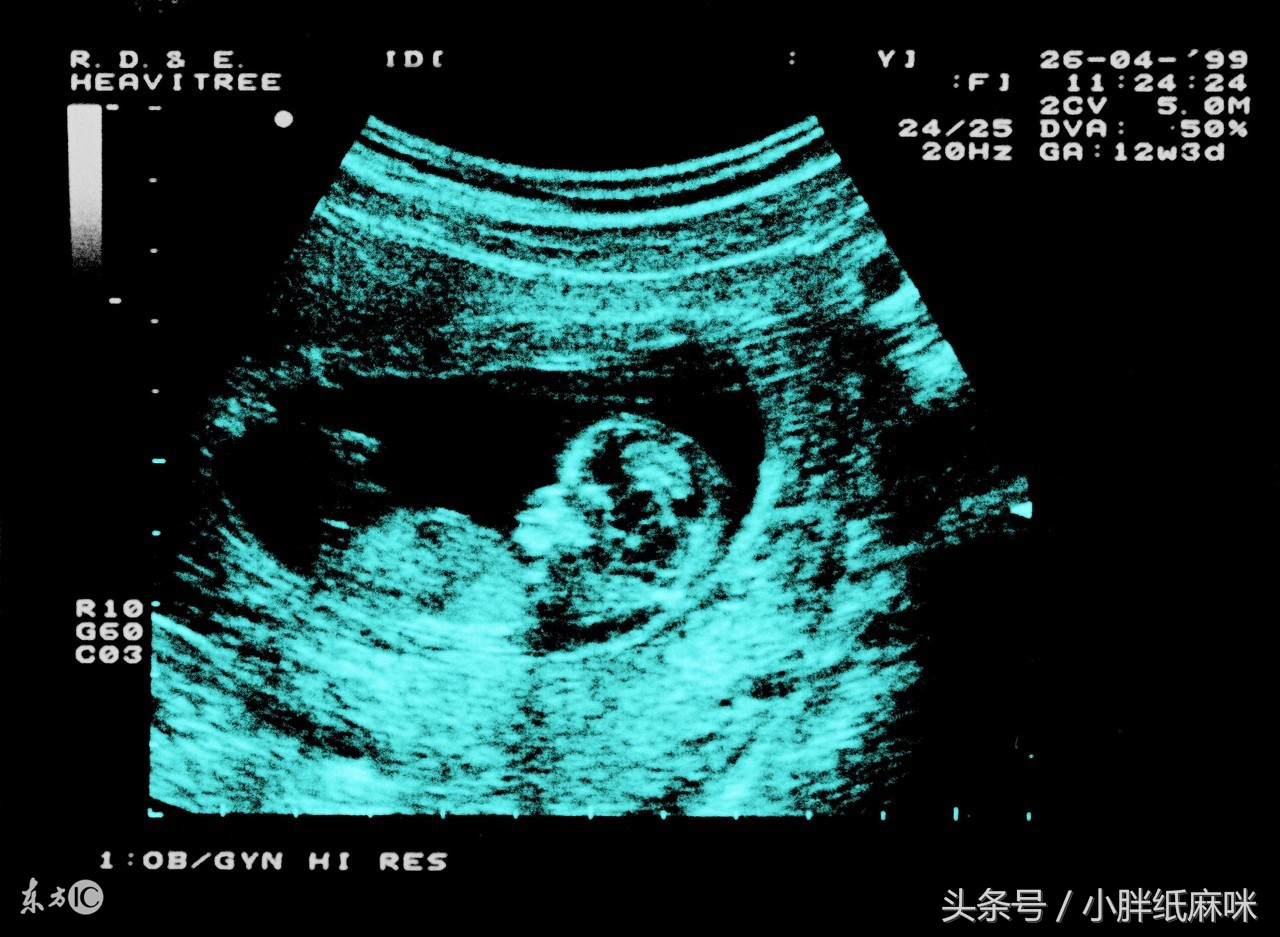

相信很多人都听说过一句话叫:“无痛人流”,引产真的可以无痛吗?

通常情况下引产都是采用药物引产的方式,通过体外将引产药物注入胎儿体内达到引产的效果。胎儿被注入药物后,由于呼吸困难但胎儿为了生存在母体内剧烈抽动挣扎,这个过程对孕妇的心里打击是无法用言语来表达的,甚至有些胎儿引产出来后还是活着的,很多女性在引产时崩溃大哭,而她们哭的并不是肉体上的疼痛,而是来自内心的刺痛,引产的情景很长一段时间里会在孕妇的脑海中如噩梦一般不断重复出现,挥之不去。